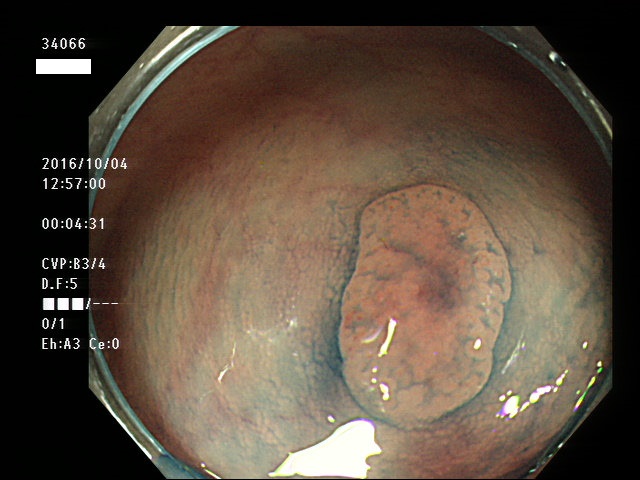

上記100名より抽出した平坦・陥凹型腺腫(=癌化の危険が高いが見落としやすい病変)の内視鏡写真